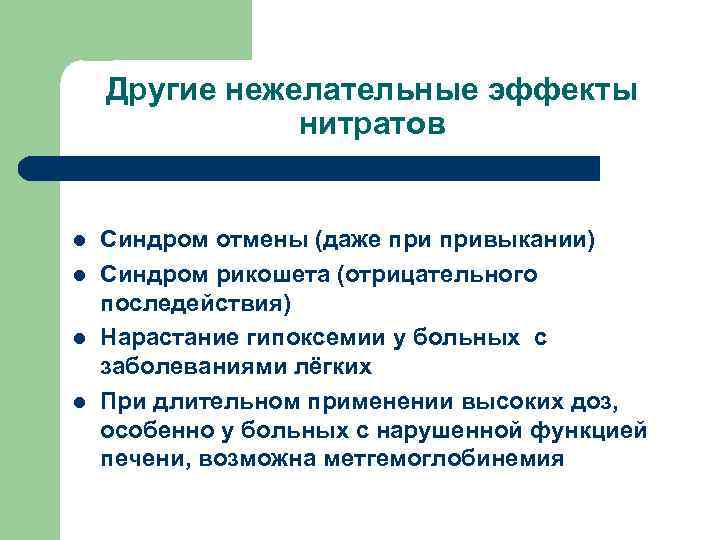

Другие нежелательные эффекты нитратов l l Синдром отмены (даже привыкании) Синдром рикошета (отрицательного последействия) Нарастание гипоксемии у больных с заболеваниями лёгких При длительном применении высоких доз, особенно у больных с нарушенной функцией печени, возможна метгемоглобинемия